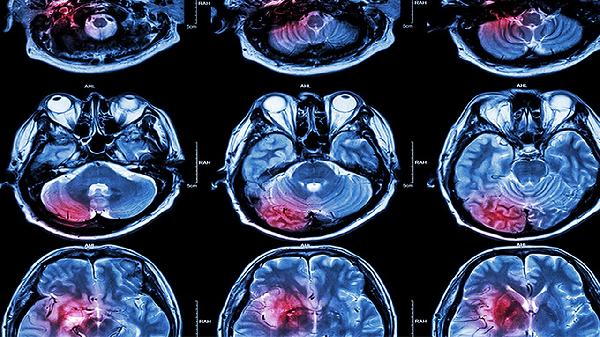

脑白质发育不良临床表现有哪些

脑白质发育不良的临床表现主要有运动障碍、认知功能下降、语言发育迟缓、癫痫发作、视觉或听觉异常等。脑白质发育不良是指大脑白质结构或功能异常,可能由遗传因素、围产期缺氧、感染等原因引起。